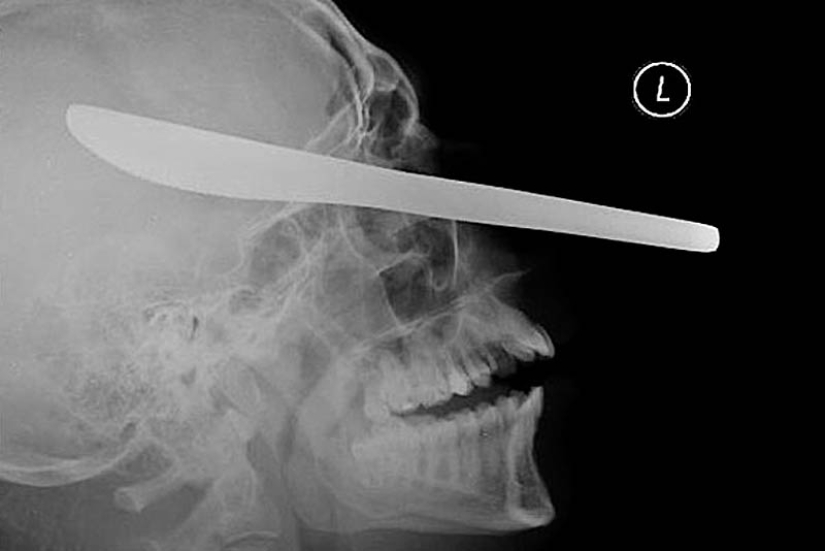

19. Un cuchillo para cortar aceite en el ojo del paciente.